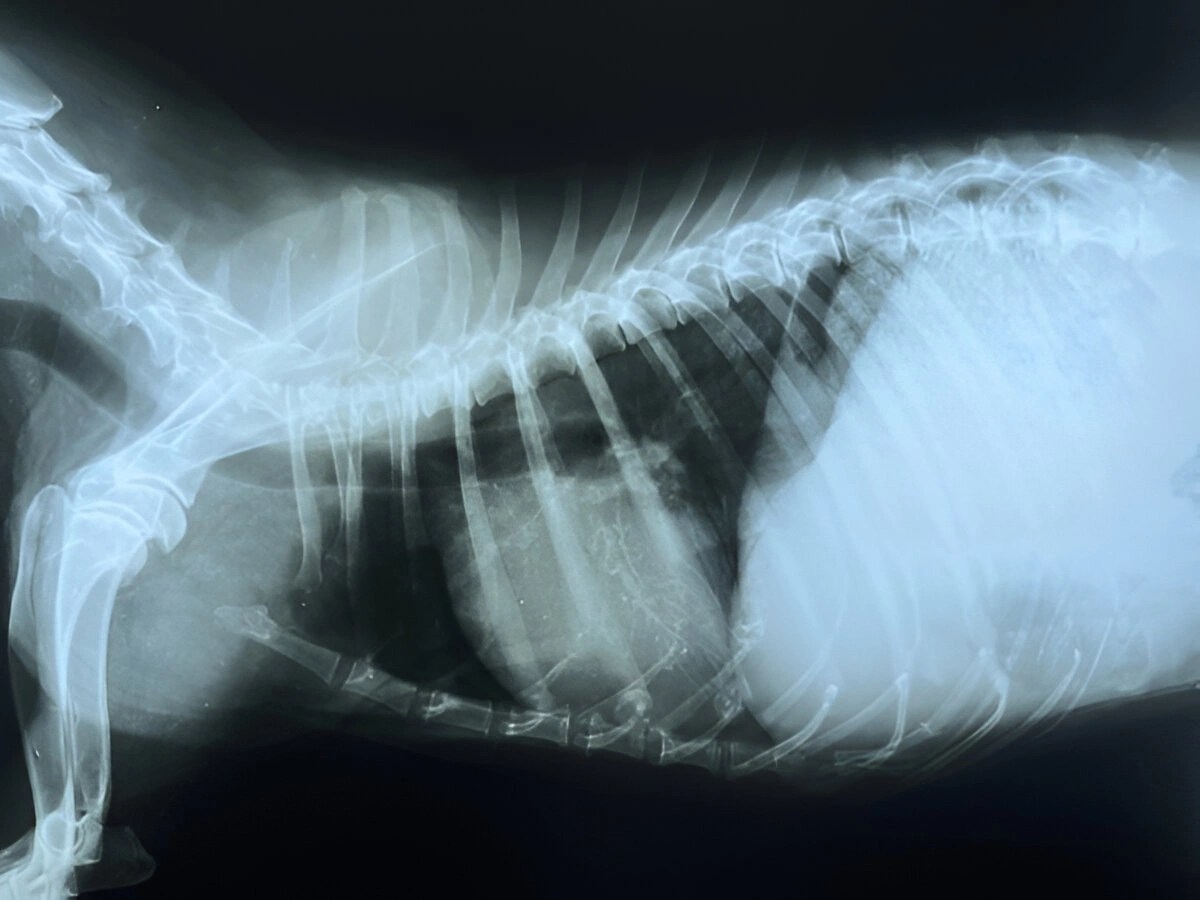

Сердце Собаки Фото

Сердце Собаки Фото 109 фото